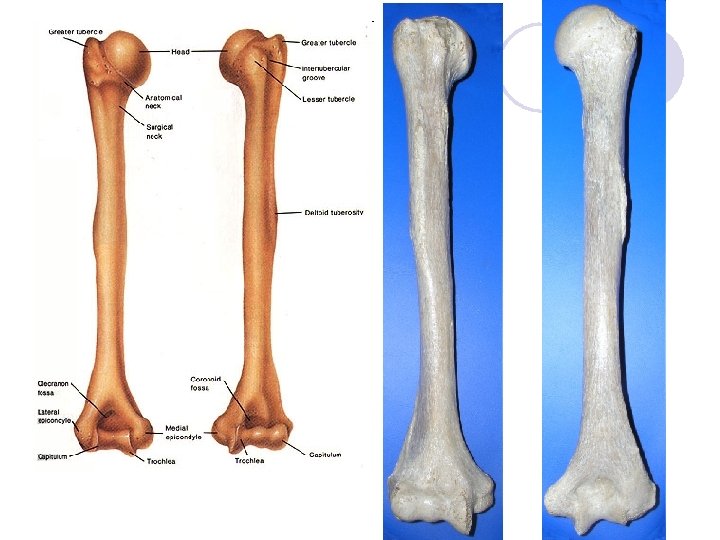

Paže - BRACHIUM l l l l Kost pažní – HUMERUS: Dlouhá kost Polokulovitá hlavice – CAPUT HUMERI Anatomický krček – COLLUM ANATOMICUM HUMERI Chirurgický krček – COLLUM CHIRURGICUM HUMERI Hrboly – velký hrbolek – TUBERCULUM MAJUS - malý hrbolek – TUBERCULUM MINUS Kladkovitá plocha – TROCHLEA HUMERI Nadkloubní hrboly – EPICONDYLUS MEDIALIS ET LATERALIS